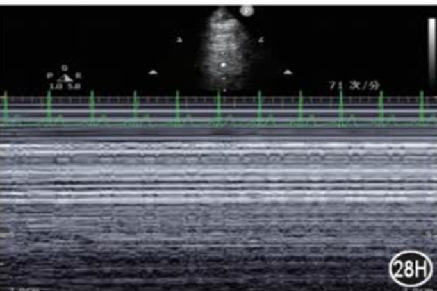

肺滑动征:①肋骨下高回声、光滑的水平线为胸膜;②正常情况下,脏、壁层胸膜紧贴,随呼吸相对滑动;③粘连或者有气体分隔脏、壁层胸膜时,胸膜滑动减弱或消失。在M型超声下的肺滑动征称“海岸征”,能更好地观察肺滑动征。肺滑动和海岸征的存在基本可以排除气胸(视频2,图7)。

图片

图7  海岸征

A线:正常肺征象的一部分,是与胸膜线平行的重复伪影,A线之间的间距等于皮肤到胸膜线之间的距离,A线出现却不伴有肺滑动征,则提示气胸的存在视频2